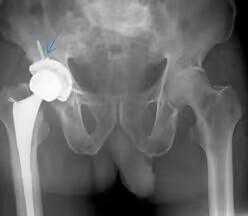

术前经过专家会诊,给出详细手术方案,完善血常规,凝血常规,感染四项等检查。在患者及家人同意后实施全髋关节置换术。术后给予预防感染,消肿,止痛等治疗,并指导患者行功能锻炼。

先天性髋关节病患者在接受髋关节置换手术后,疼痛可以得到缓解,关节活动度可以提高。患者在术后需要进行一定的康复训练,包括肌肉训练、关节活动度训练等,以促进关节功能的恢复。同时,患者需要定期回诊复查,接受医生的指导和治疗。

专家介绍,髋关节置换手术是一种复杂的手术,术后恢复需要一定的时间和正确的护理。通过术后康复,患者可以最大限度地恢复髋关节功能,减少并发症的发生,提高生活质量。康复的目标包括恢复关节活动度、增强肌肉力量、提高平衡和协调能力以及改善日常生活能力。其次,术后应进行的物理治疗和训练方法。在手术后的一到两周内,患者可以在医生的指导下进行关节活动和肌肉锻炼,如屈伸关节、抬腿等。这些活动可以帮助预防关节僵硬和肌肉萎缩。总之,对于先天性髋关节病患者,如果病情严重,可以考虑接受髋关节置换手术。选择经验丰富的医生和专业的手术团队进行手术,术后积极进行康复训练和定期回诊复查,有助于提高手术效果和改善患者的生活质量。